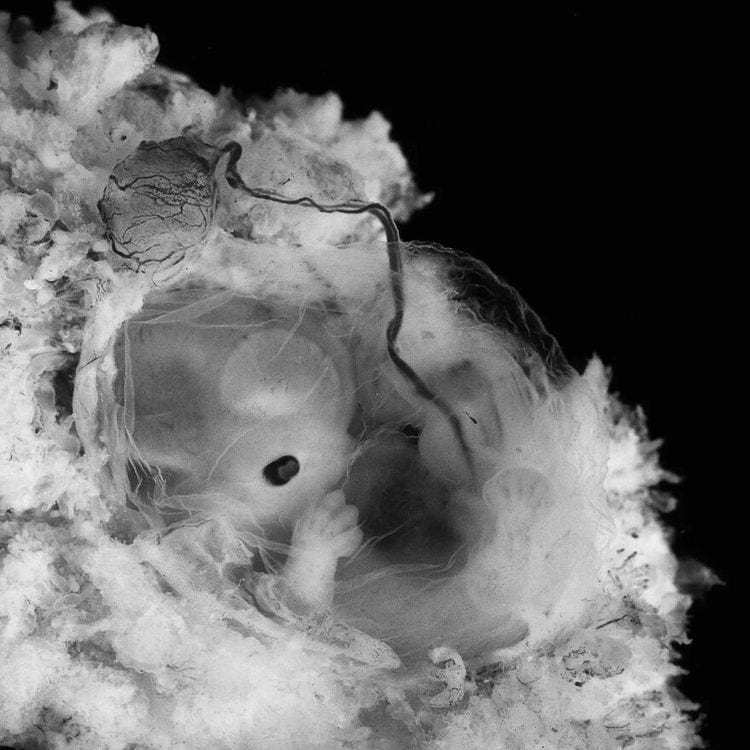

Пять недель, 1990 год

7 недель, 1990 год